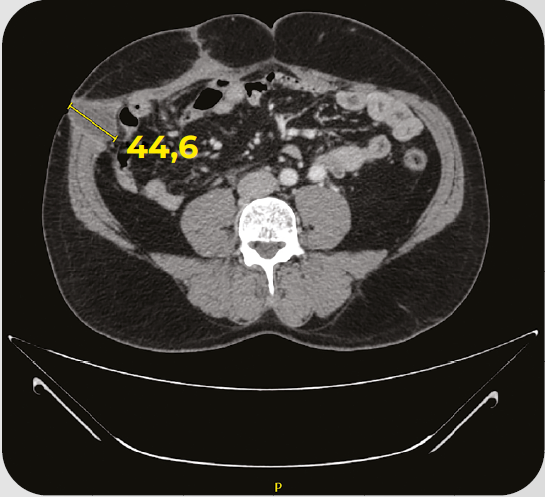

Caso clínico: paciente com CRC MSI-H O Caso clínico em questão, traz detalhes sobre o tratamento em 1L de pacientes com câncer colorretal metastático com deficiência de enzimas do reparo (dMMR)/alto nível de instabilidade de microssatélites (MSI-H).